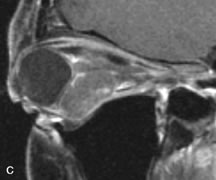

Cystic Lesions

Dermoid cysts appear as rounded, well-defined lesions typically contiguous with an orbital bony suture. The high-intensity signal on T1-weighted images is attributed to the sebaceous-produced lipid contents (Fig. 18).31,50 Mucoceles may demonstrate a hypointense or hyperintense signal on MR images, depending on the concentration of proteinaceous or inflammatory fluid components. The integrity of the bony walls of the expanded sinus cavities cannot be assessed on MR as well as by CT.37,50,55,56 A high-signal intensity on Tl- and T2-weighted images is characteristic of orbital chronic hematic cysts because of the blood-breakdown products within the cysts.57

Fig. 18. A. T1-weighted, (B) T2-weighted fat-suppressed, and (C) T1-weighted fat-suppressed MR scans demonstrate a small dermoid cyst arising near the palpebral portion of the lacrinal gland (arrows). The lesion is similar in signal intensity to fat on the T1-weighted scan (A) consistent with a high adipose tissue content. The lesion shows fat-suppression and low signal intensity on the two fat-suppressed sequences (B and C) confirming its high lipid content.